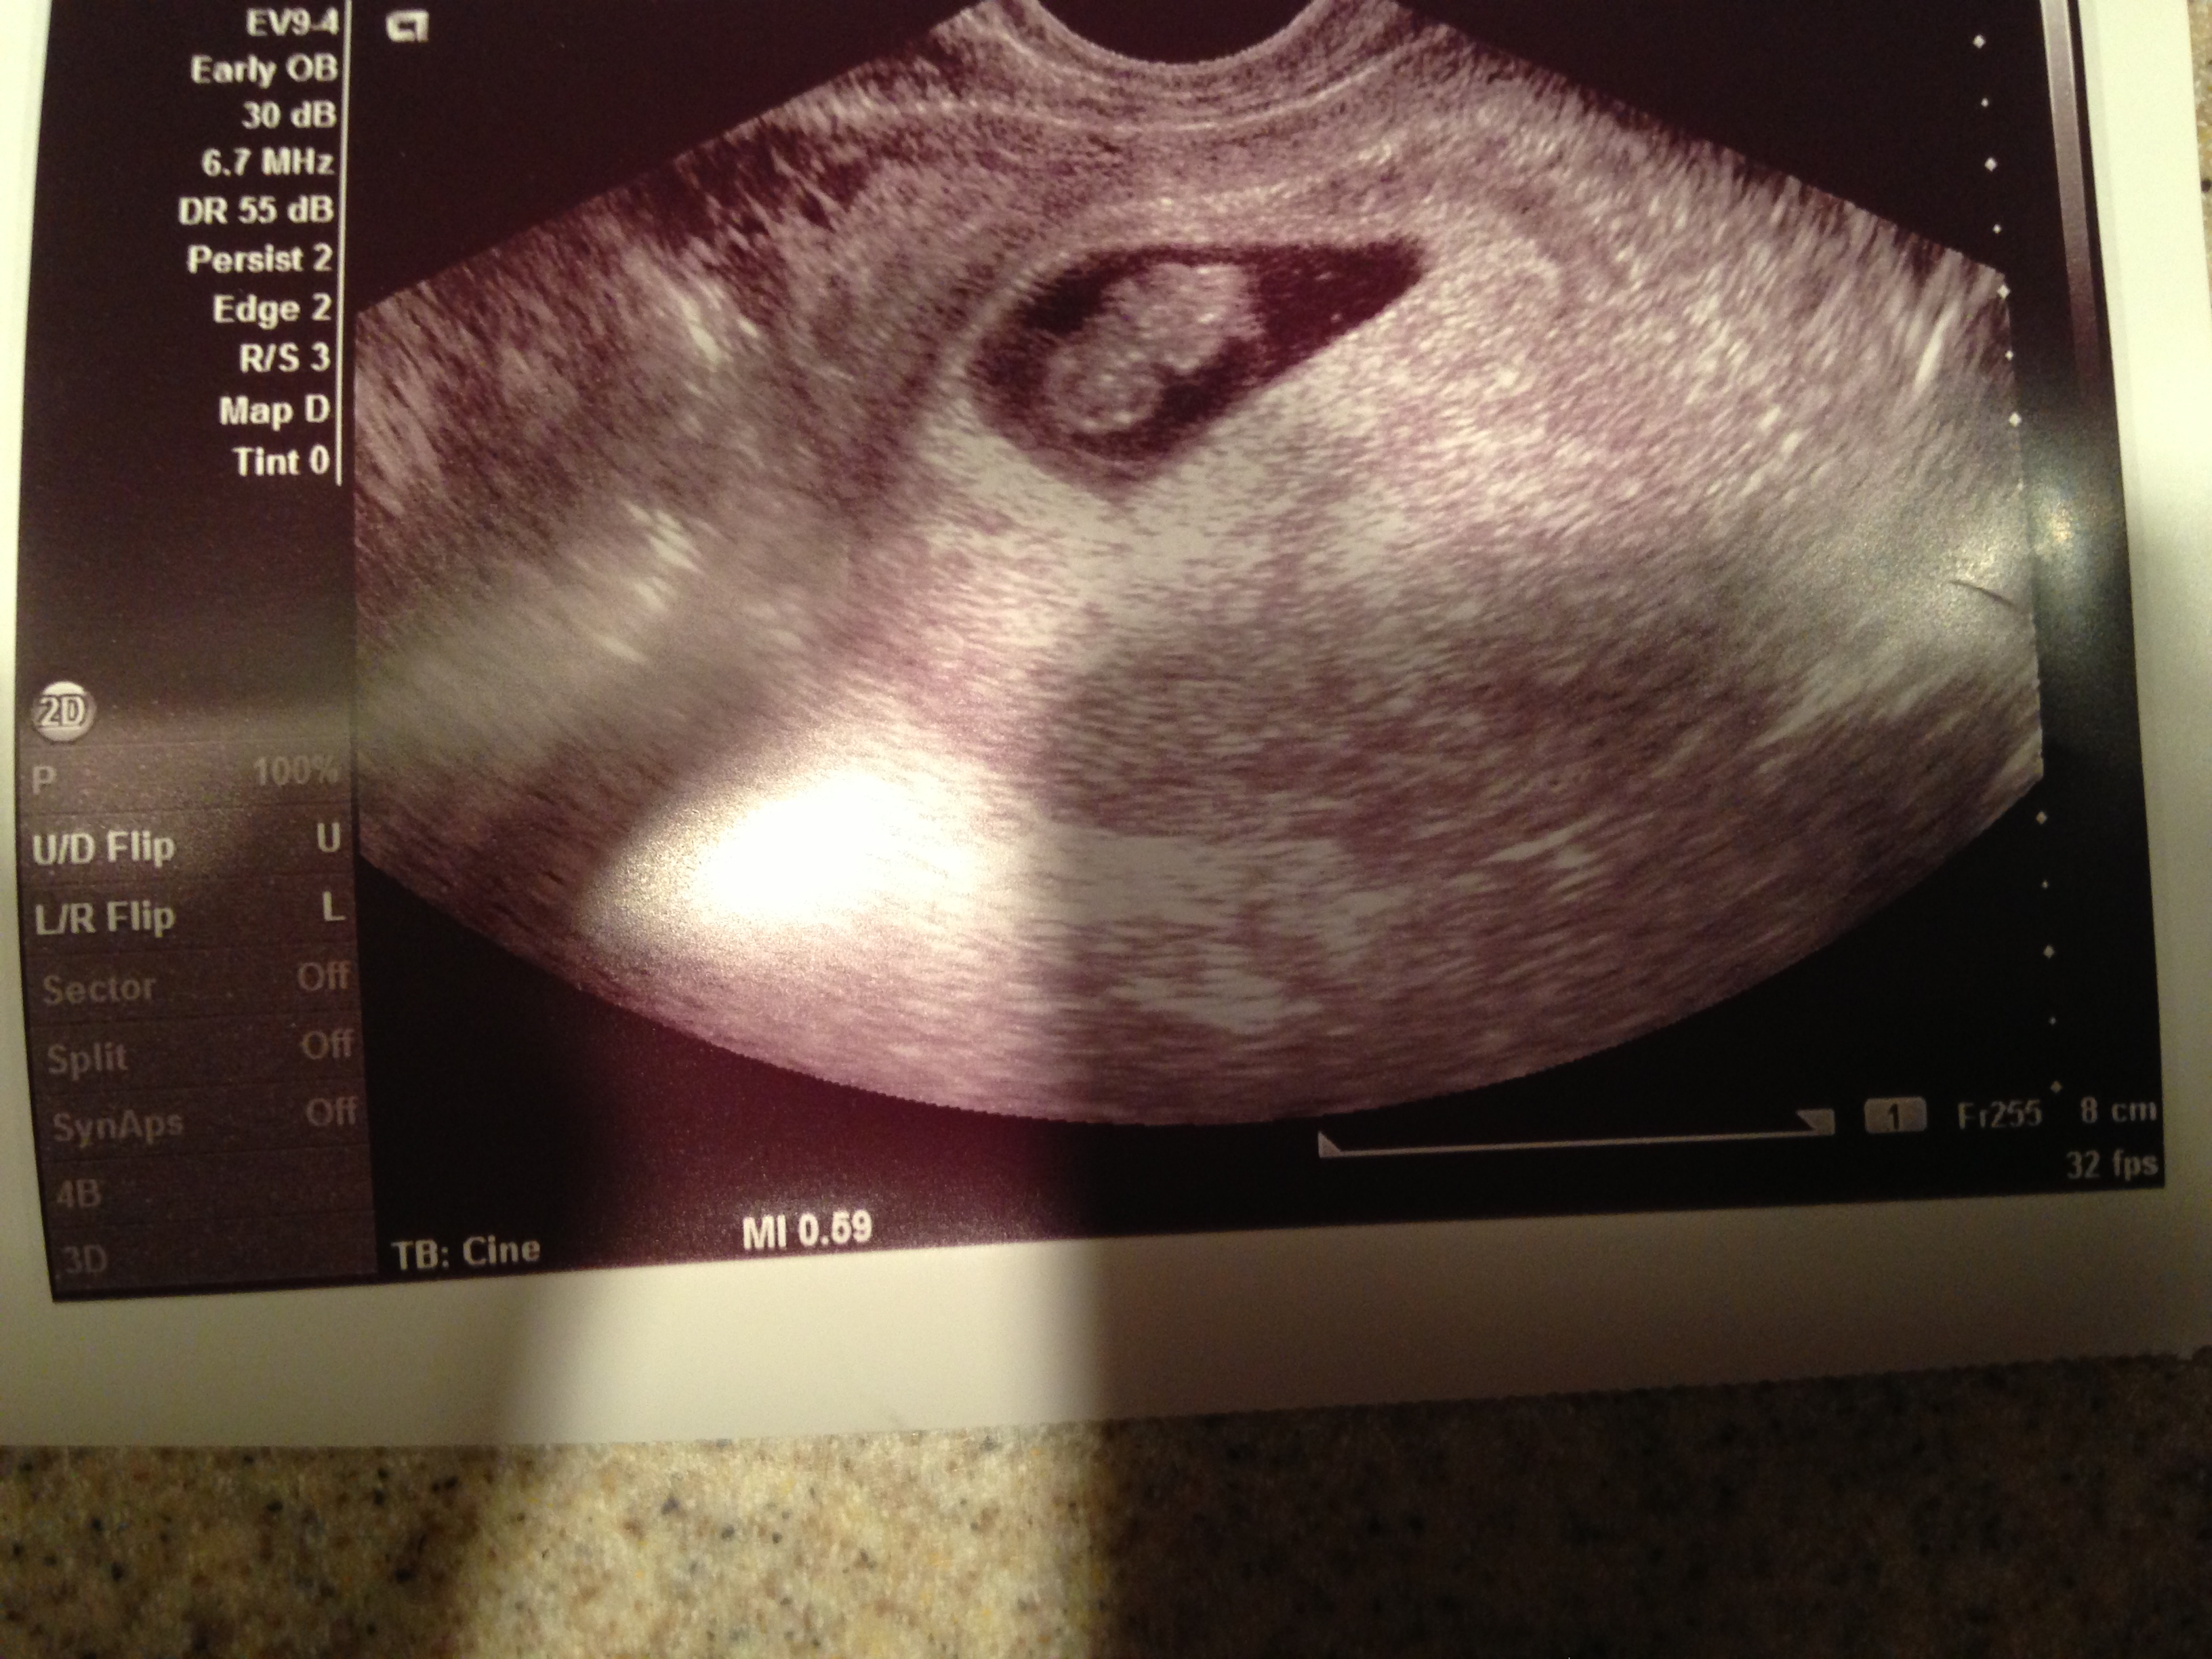

Here is our ultrasound picture from yesterday!

Noodle was measuring right on track at 8w1d. Heartbeat was 179 beats per minute!

@KH826 - I've been looking forward to hearing about your first u/s!! I am so, so glad everything looks perfect

I'm SOOOOOO happy for @kh826 for getting to hear the heartbeat and getting the ultrasound pic.

@KH826 - I loved when I saw my little guy at that stage - it did get very real! He looked like a little teddy bear. Wait until the next one - mine was at 10 weeks and my mind was blown at the difference. Thinking of you and your LO & a continued healthy pregnancy!

@KH826 beautiful beautiful mini-baby! So excited for you!